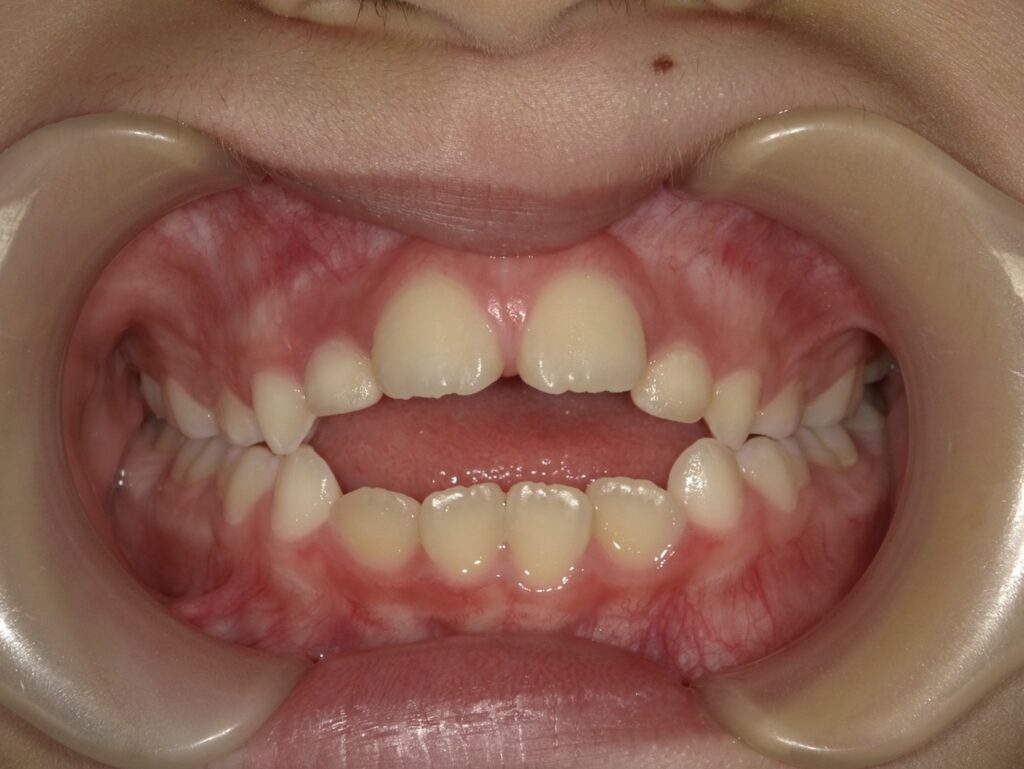

具体的には

・上顎前突(出っ歯)

・開咬(前歯で咬めない、オープンバイト)

・臼歯部の交叉咬合(奥歯が正しく咬んでいない、クロスバイト)

のような不正咬合の原因となってしまいます。

指しゃぶりをしていると物理的に上下の前歯に常に指が介在することで前歯に空間が生じます。これが開咬です。

また、指を吸うことで上の歯並びに頬圧がかかり歯列の幅が狭まります。これはV字状の歯列とも言われ、結果として上の前歯は前方へ出て上顎前突を引き起こします。

下の歯並びより上の歯並びの幅が狭いと、臼歯部の交叉咬合となります。